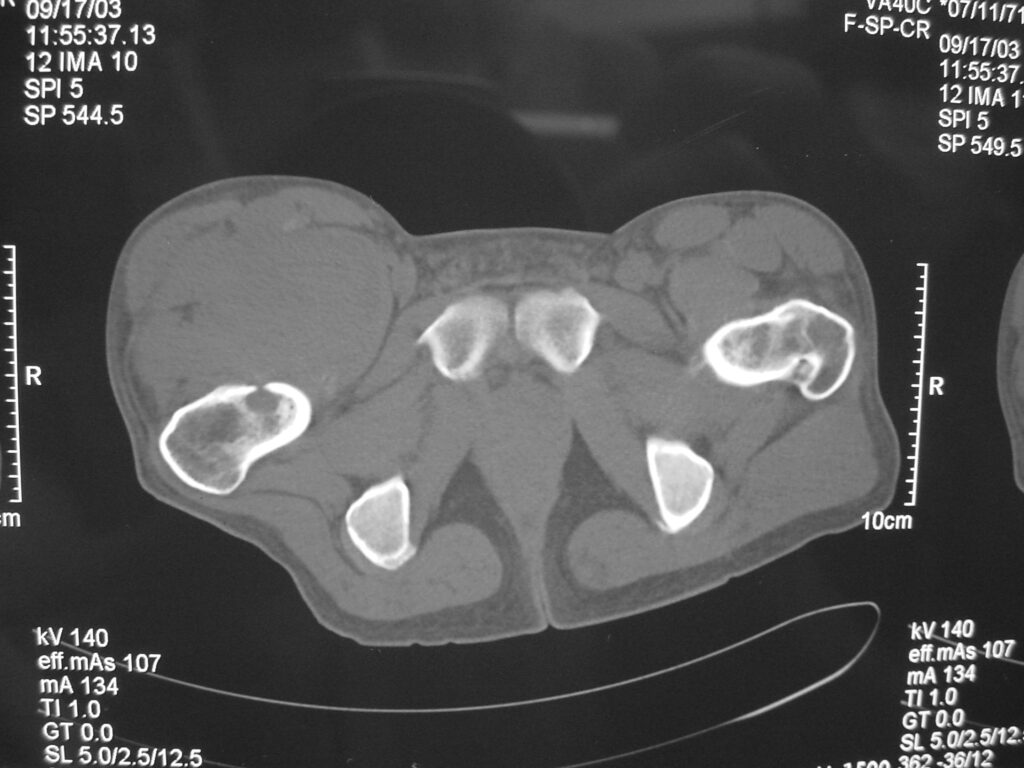

X-rays

Soft tissue density with mineralization in 30% of cases. This type of mineralization usually presents as calcifications with an irregular contour often in a peripheral distribution.

In 11% to 20% of cases there may be a periosteal reaction, adjacent bony erosion or bone invasion.